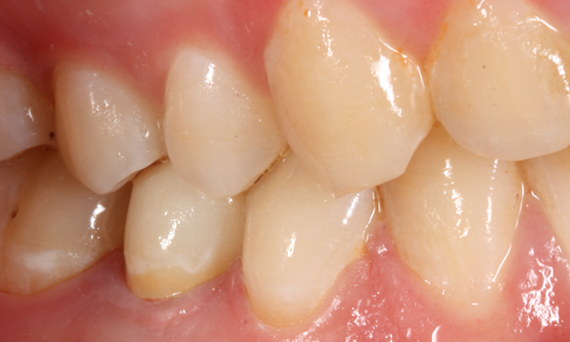

Before

Insufficient fillings in the second quadrant. The restorations were about 15 years old.

After

Chairside-fabricated crowns made from CEREC Tessera (teeth 26/27). Inlays for teeth 24 and 25 made of composite blocks.